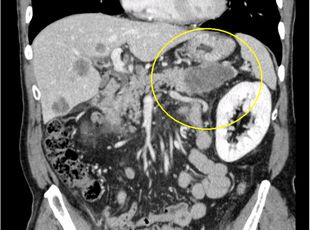

造影CT CPR像(膵尾部がん)